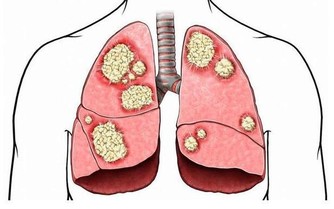

5. 其他癌症,患有膀胱癌、肺癌或甲狀腺癌的患者,出現前列腺癌的風險較高。